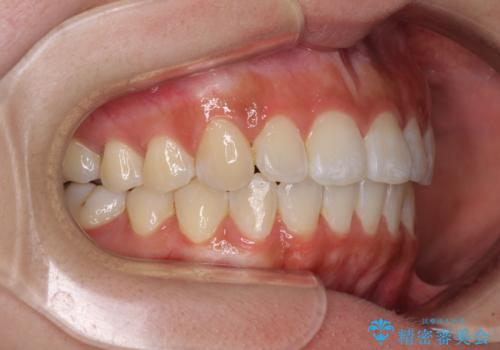

- 上下前歯のデコボコを気にして来院された患者様です。

インビザラインによる上下歯列の拡大と、IPR(歯と歯の間を削る)にるスペースの獲得により、前歯のデコボコを改善することとしました。